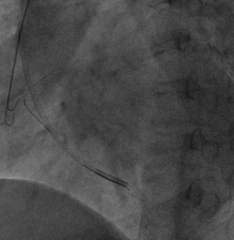

手术经过:首先冠脉造影延迟显影可见冠状窦开口及靶静脉大致走行

AP

LAO45

6225i球囊造影可见轻微夹层,远端未显影

6250VIS鞘管直接造影可见分支显示良好

LAO